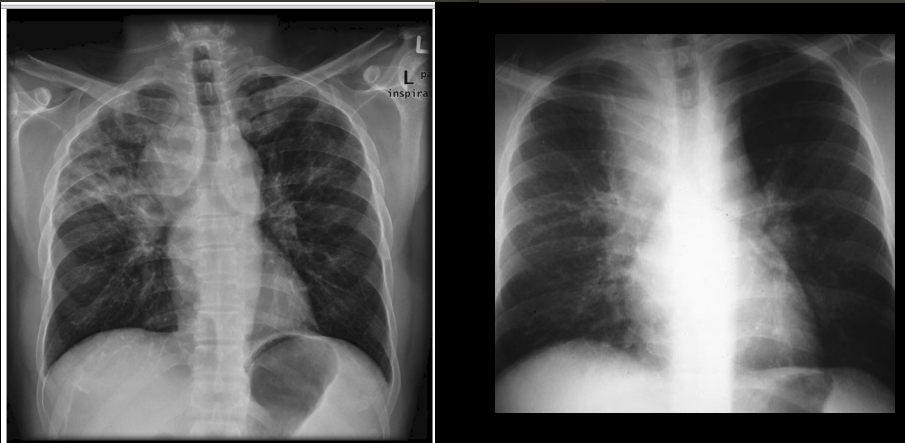

✅Туберкулёз у ВИЧ+ больного отличается на вид от таких же форм туберкулеза у ВИЧ-отрицательного: на рентгене его можно принять за онкологию или пневмоцистную пневмонию, например. И это еще сильнее затрудняет диагностику.

Слева саркаидоз у обычного пациента, справа - туберкулез у ВИЧ+ пациента. Источники [1] и [2].